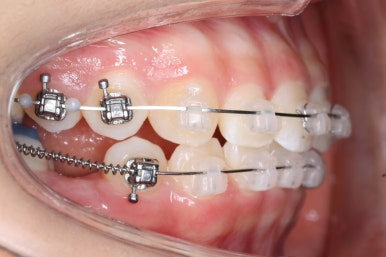

아래쪽이 더 시급하므로 브라켓 부착을 하여 가지런히 하기 시작했고 위쪽은 악궁확장장치를 입천장에 하여 위턱뼈를 가로로 넓혀주기 시작합니다.

윗니에도 이제 장치를 모두 붙였습니다. 아래쪽은 어느 정도 가지런해지고 나면 부족한 자리를 만들어주기 시작합니다.

부산치아교정잘하는곳 키다리아저씨치과에서 이번 환자분에 사용한 장치는 데이몬 클리어라고 하는 세라믹 자가결찰 장치입니다. 세라믹 자가결찰 장치 중에서 철사를 잡아주는 CAP 부위까지 세라믹으로 되어있어 가장 심미적인 장치라고 볼 수 있습니다.